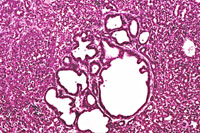

A proliferative cystic biliary lesion, a solid basophilic adenoma, and a bile duct adenoma in a 4-week-old transgenic mouse.